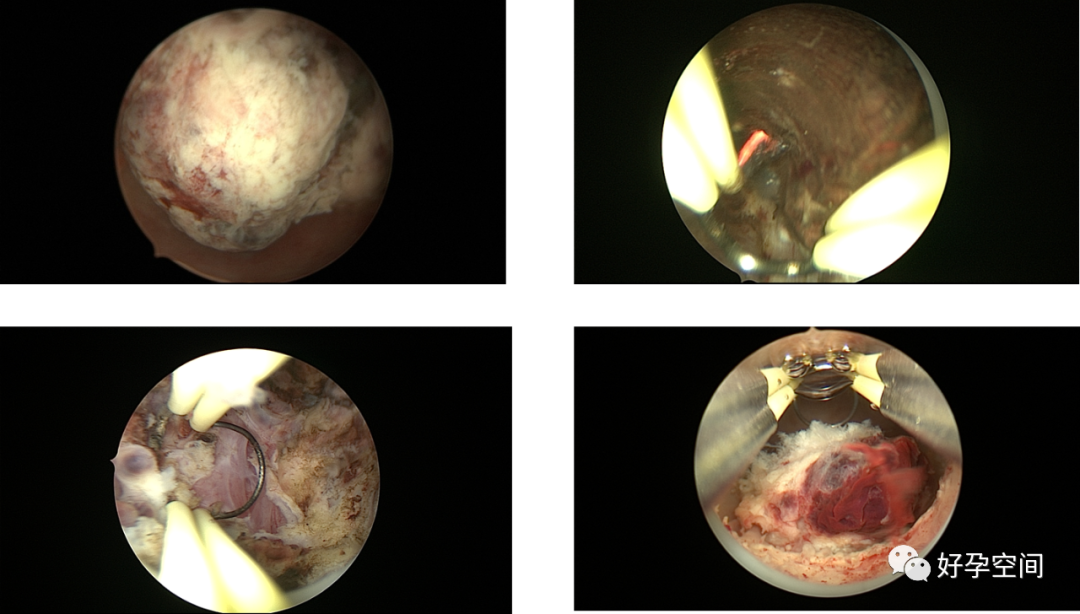

4、取胚、人流及药流不全、带环受孕、切口妊娠、宫角妊娠、切口憩室、宫颈妊娠,胎盘残留、胎盘粘连、胎盘植入、子宫动静脉瘘手术。

宫腔镜下的胚胎

胚物残留、左侧宫角妊娠、切口妊娠、切口憩室

胎盘残留、胎盘粘连、胎盘植入、动静脉瘘